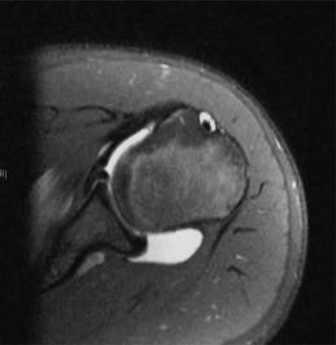

CASE 9 A 14-year-old boy is brought to the ER with complaints of right knee pa…